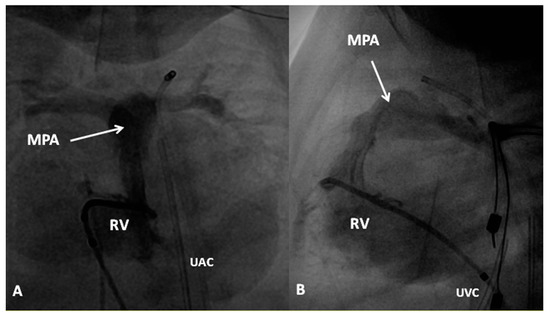

3.1. TGA with Intact Ventricular Septum

In TGA with intact ventricular septum, there are no other intracardiac defects other than persistent fetal structures such a patent foramen ovale (PFO) and PDA. If there is adequate mixing across PFO and/or PDA, the infant maintains adequate O2 saturation; if not, the infant will present with hypoxemia. Intravenous infusion of PGE1 (0.05 to 0.1 mcg/kg/min), as described in the preceding sections, may help open the ductus and improve O2 saturation. If there is no improvement, balloon atrial septostomy (Figure 6) [41,42] is performed. In most cases, balloon atrial septostomy is successful with occasional need for blade septostomy [42,43].

Two types of surgical strategies, namely venous switch [44,45] and arterial switch [46] have been described to correct TGA. Venous switch procedures such as Senning [44] and Mustard [45] were used extensively in 1960s, 1970s and 1980s, but because of atrial arrhythmias during follow-up and leaving the right ventricle as systemic ventricle, gradually, arterial switch procedure was adopted as procedure of choice in late 1980s and there afterwards. The Jatene (arterial switch) along with the LeCompte maneuver [47] is usually performed around the age of one week. Consequently, balloon atrial septostomy may not be needed in all infants. If naturally occurring PFO and/or PGE1 infusion to open the ductus arteriosus do not maintain adequate O2 saturations (60% to 70% without metabolic acidosis), balloon atrial septostomy is required preparatory to the Jatene procedure. More recently, some groups of surgeons have been performing the Jatene procedure within the first few days of life, avoiding the need for balloon atrial septostomy altogether.

At the time of presentation, usually in the early infancy, palliation depending the physiological abnormality (modified BT shunt or pulmonary artery banding) (Figure 7) is performed after initial stabilization.

At about the age of six months, a bidirectional Glenn procedure [80] is performed. In this procedure, the superior vena cava (SVC) is disconnected from the right atrium and anastomosed to the PA so that the blood from SVC is directed into both branch PAs, thus the name bidirectional Glenn (Figure 8).